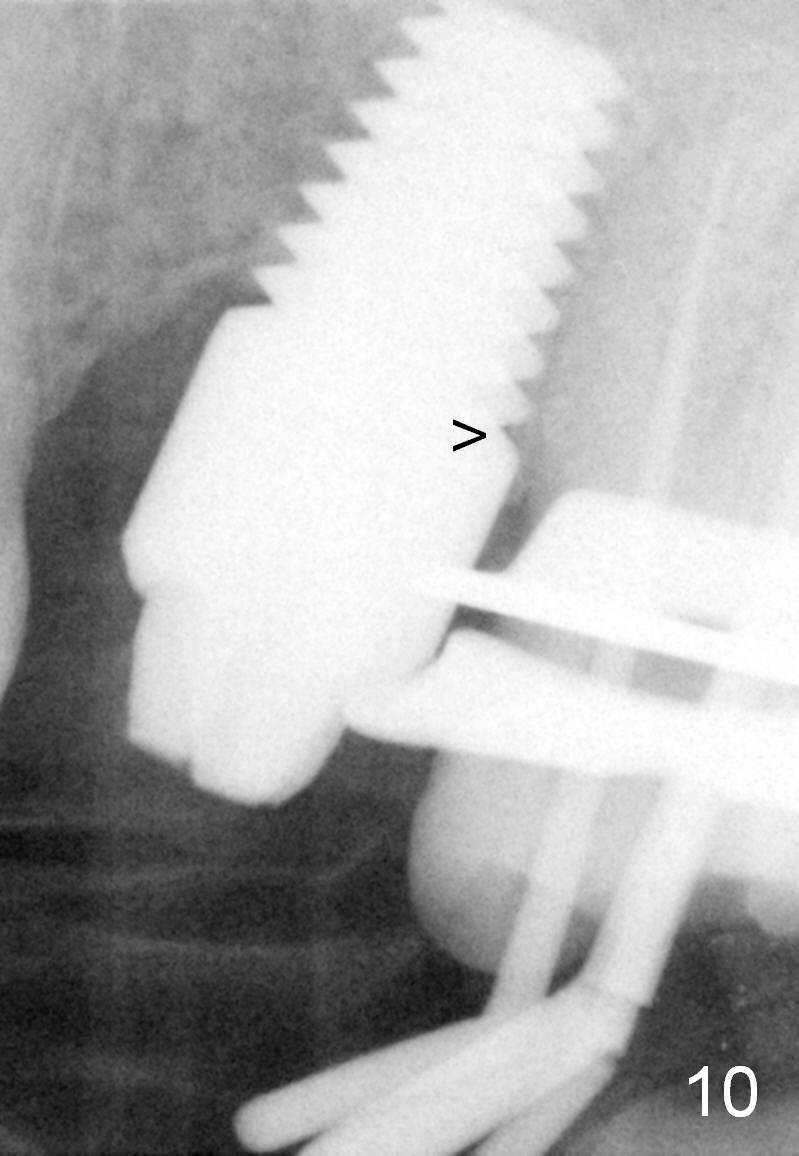

Twenty-one months postop, the patient returns for #15 RCT. PAs show that although there is a narrow space in the original mesial socket (Fig.9 *), the 1st thread space is partially obliterated with the bone (<). In contrast, the distal 1st thread space is completely obliterated (Fig.10 >). After the RCT, impression is taken for #14 and 15. Although there is no sign of periimplantitis, the 7x14 mm implant looks too large for the site with possible buccal thread exposure 4 years 9 months post cementation (Fig.11). To reduce complications, a much small fixture will be at #30.